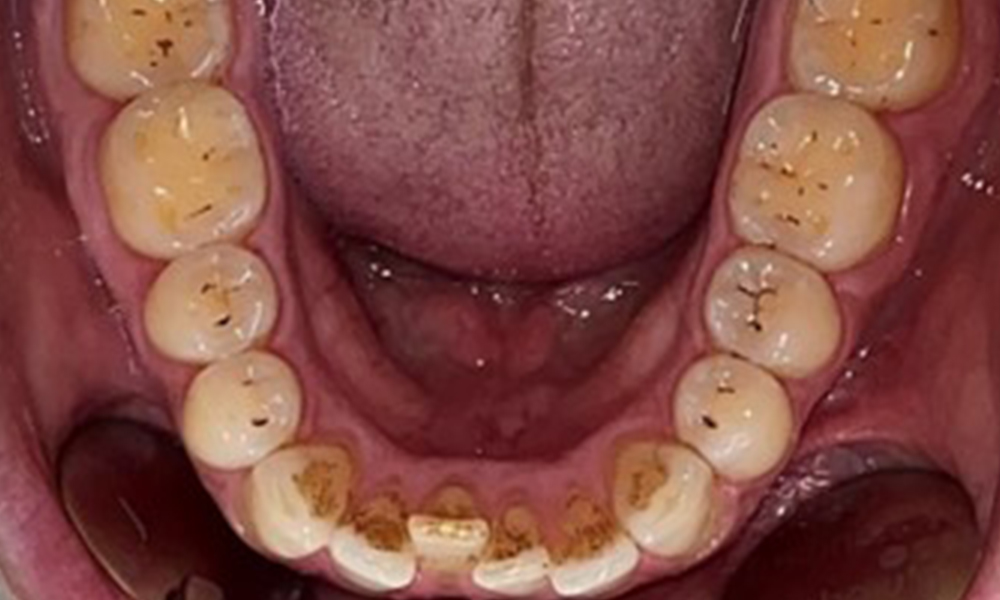

The patient has full dentition with a total of 28 teeth. There were noteworthy erosions and attritions. (Fig. 4, Fig. 5). Due to bruxism, the patient has been wearing a splint with an adjusted bite block at night for many years. The erosions were caused by long-term consumption of isotonic beverages. No periodontal bone loss or active caries were observed.